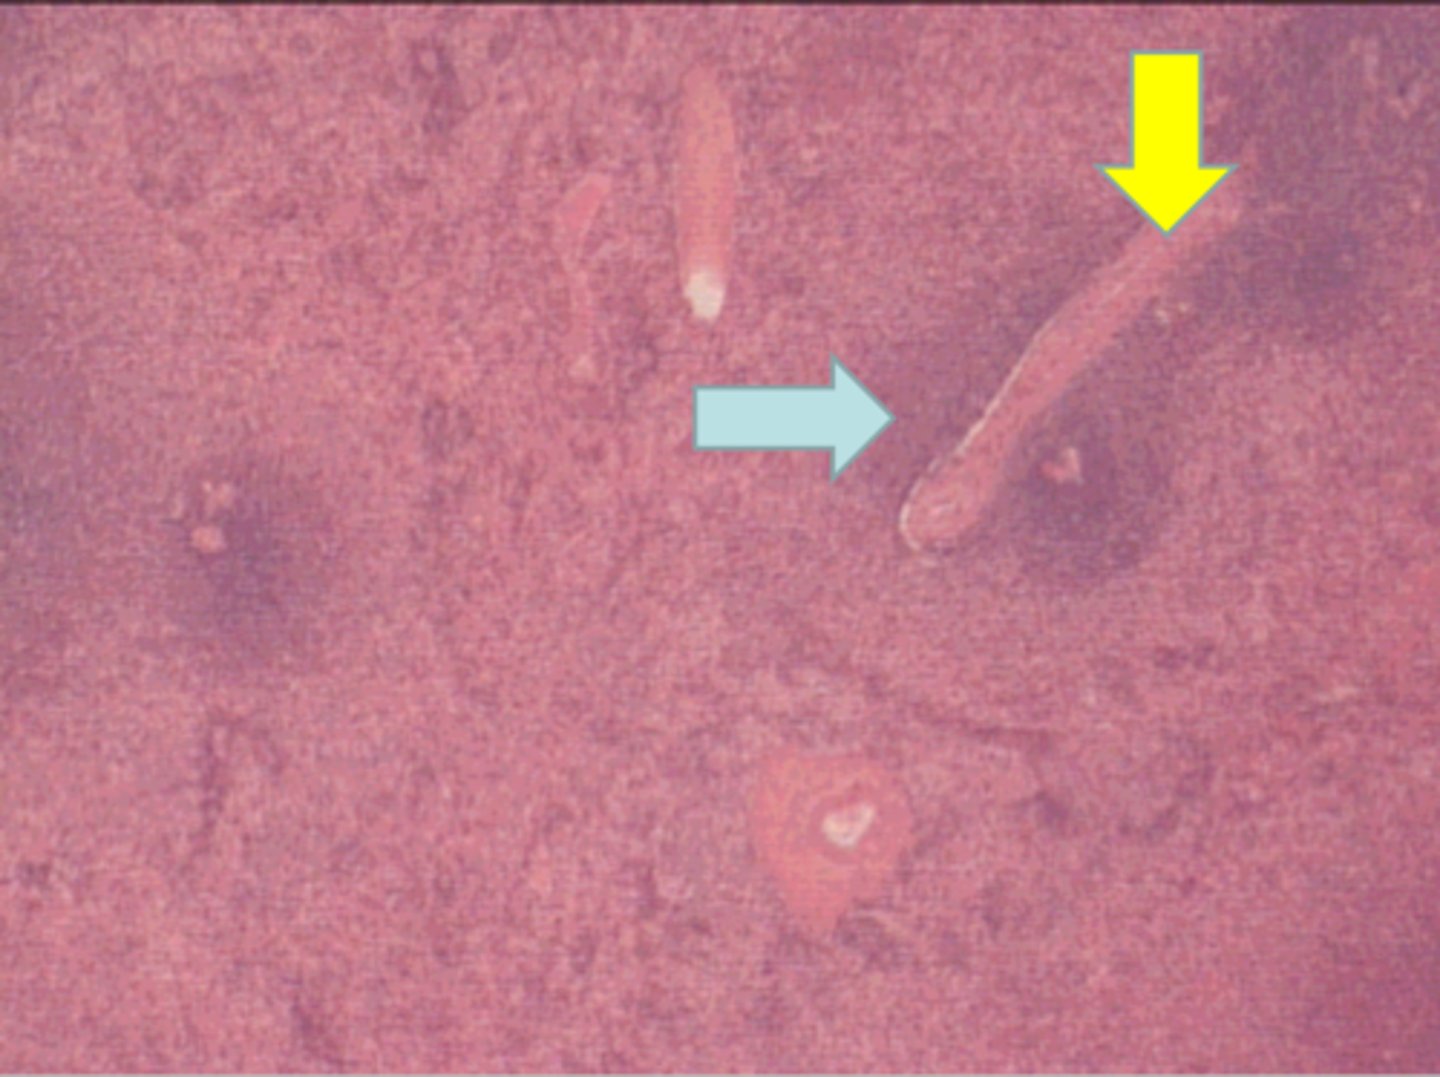

Peyer's patches in ileum

collection of secondary lymphatic nodules

ID structure

secondary lymphatic nodule

black arrow

Peyer's patches